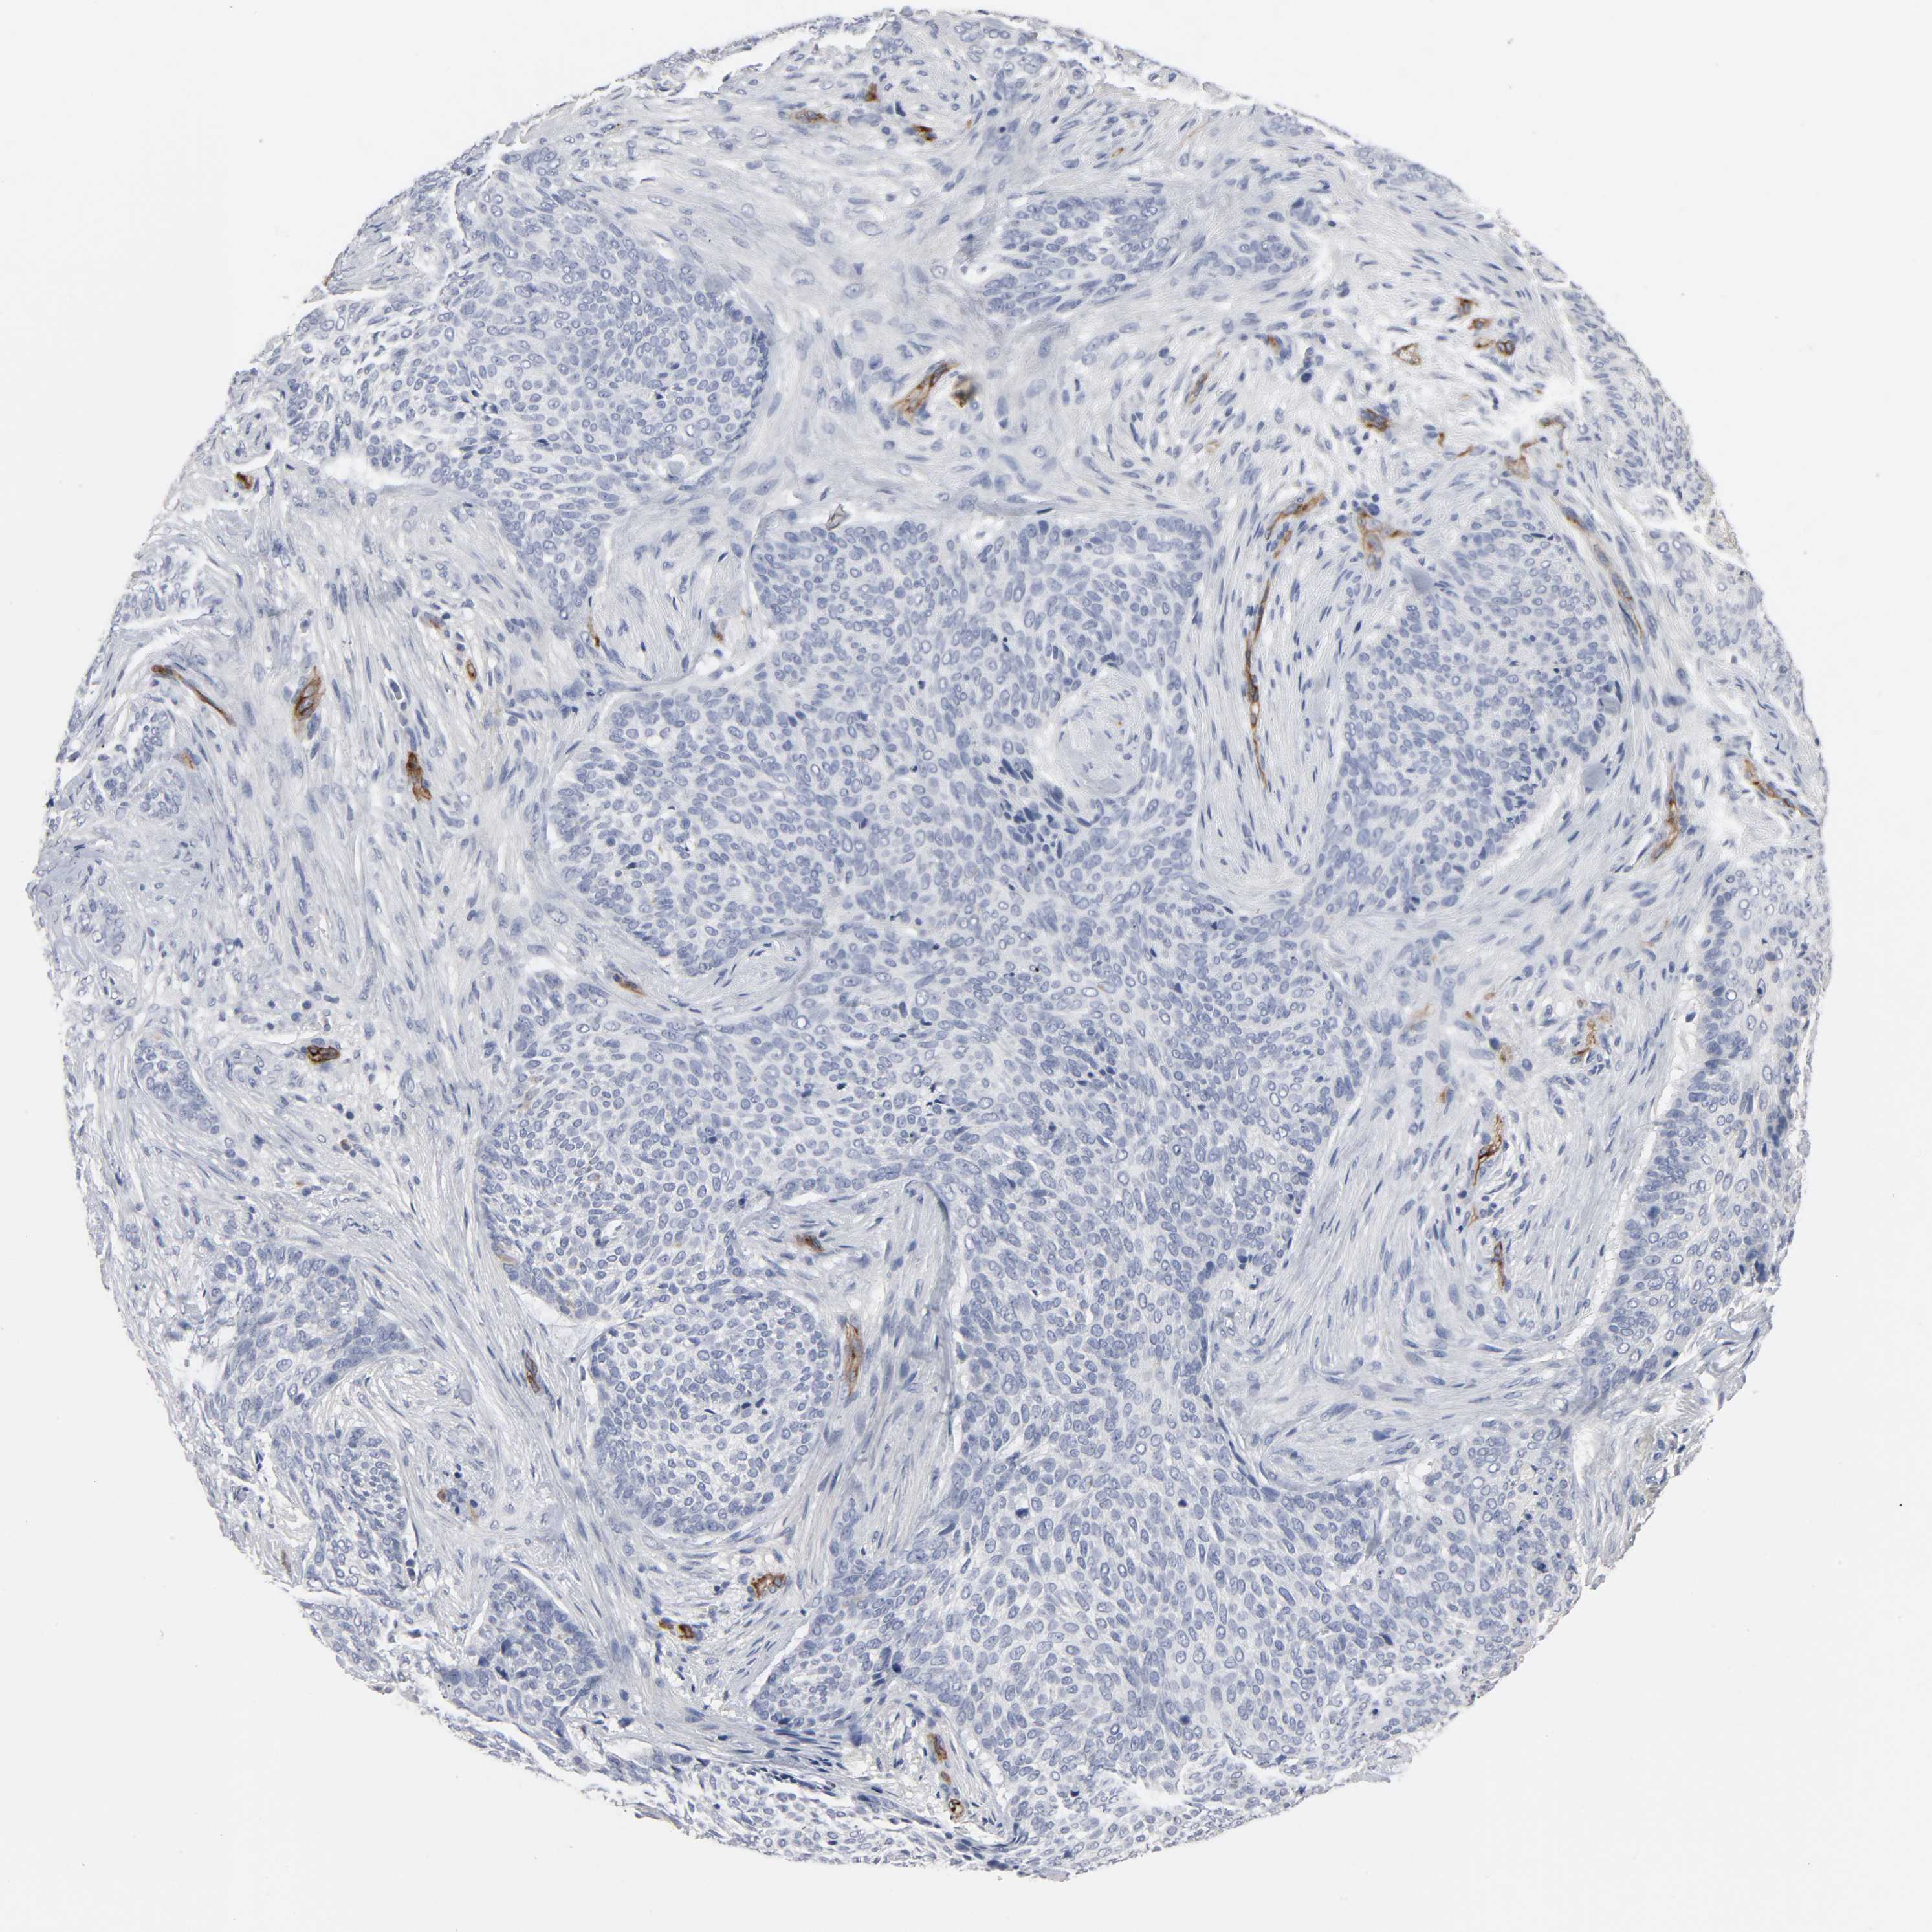

SKIN CANCER - Protein expressioni

A mouse-over function shows sample information and annotation data. Click on an image to view it in a full screen mode. Samples can be filtered based on level of antibody staining by selecting one or several of the following categories: high, medium, low and not detected. The assay and annotation is described here.

Antibody stainingi

Antibody staining in the annotated cell types in the current human tissue is reported as not detected, low, medium, or high, based on conventional immunohistochemistry profiling in selected tissues. This score is based on the combination of the staining intensity and fraction of stained cells.

Each image is clickable and will lead to virtual microscopy that enables deeper exploration of all samples and also displays staining intensity scores, fraction scores and subcellular localization as well as patient and tissue information for each sample.

Antibody CAB004028

Intensity

Strong

Moderate

Weak

Negative

Quantity

>75%

75%-25%

<25%

None

Location

Nuclear

Cytoplasmic/membranous

Cytoplasmic/membranous,nuclear

Squamous cell carcinoma, NOS

Basal cell carcinoma